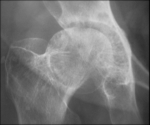

The adrenal CT scan revealed a well-defined right adrenal mass measuring 46 x 33mm, spontaneously hypodense taking the contrast product heterogeneously, the left adrenal was normal non-hypertrophic (Figure 1). As complications of her hypercorticism, the patient had diabetes, dyslipidemia, hyperuricemia, high blood pressure, diffuse bone demineralization complicated by aseptic necrosis of the right femoral head diagnosed on standard radiography of the hip (Figure 2) and pelvic scan and for which she was put on discharge and bisphosphonate treatment for osteoporosis. Once the diagnosis of ACTH independent Cushing's syndrome was reached, a right adrenalectomy was performed by laparoscopy, the postoperative consequences were simple with, as a sign of remission, the occurrence of acute adrenal insufficiency on the third postoperative day, which has been substituted.

Figure 2: aseptic necrosis of the hip on radiographs